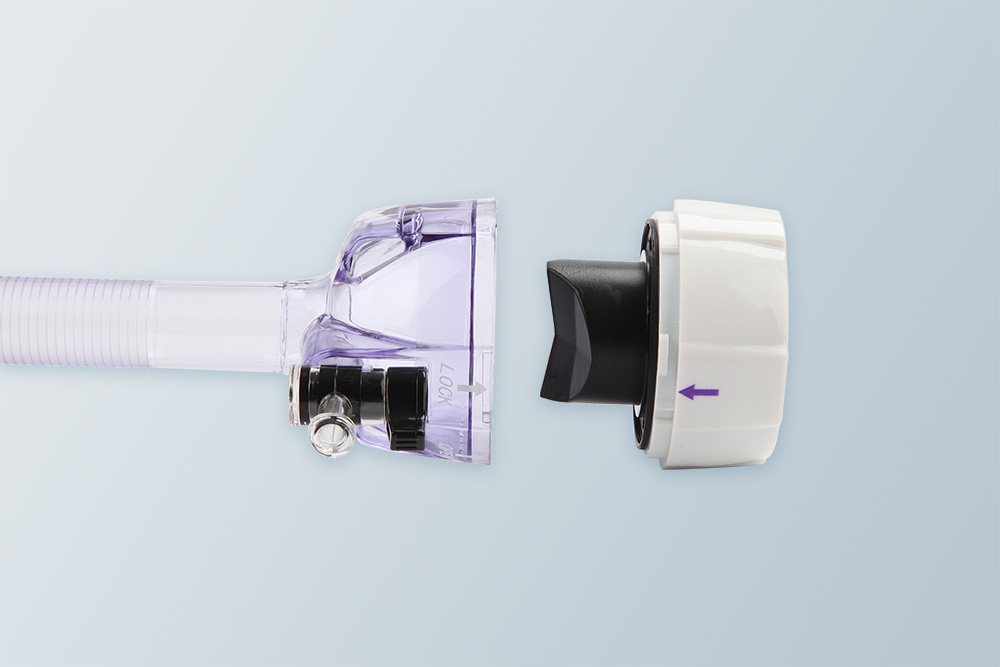

整体气密组件 取下气密组件,直接从鞘管内取出标本和缝钉,

避免标本污染

避免标本污染

双重密闭阀膜 器械插入力和拖拽力小,气密性好,

适用5~12毫米器械

适用5~12毫米器械